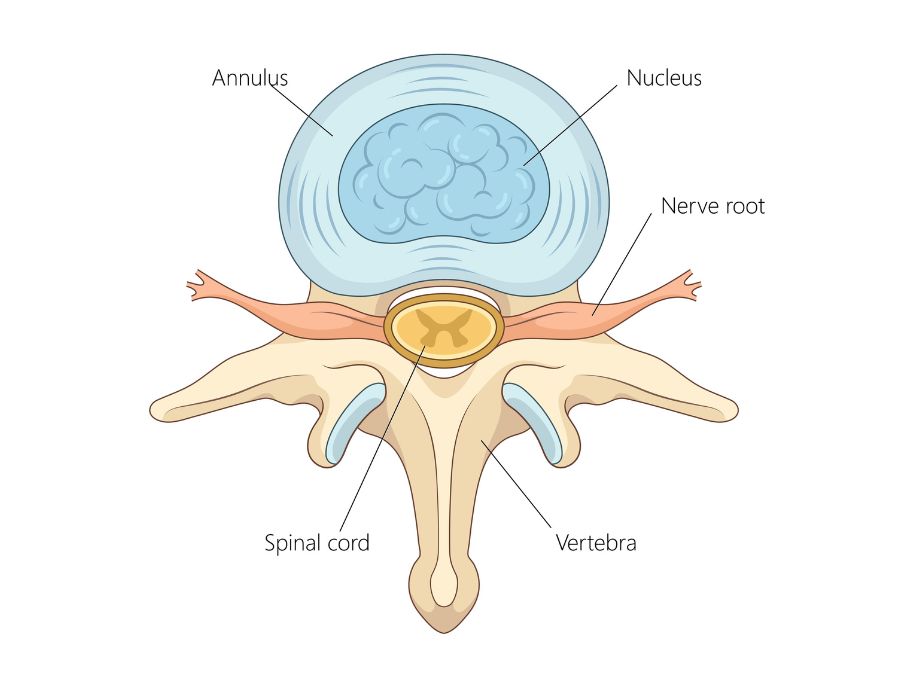

Attraverso l’Amplificatore di brillanza, l’ago è posizionato nel punto di uscita del nervo infiammato dal canale spinale, a pochi millimetri dall’ernia.

La miscela di ossigeno e ozono arriva esattamente sulle radici nervose sofferenti e sul disco, normalizzando il livello di citochine e prostaglandine con effetti antinfiammatori e antidolorifici. La stretta vicinanza della miscela di ozono al materiale erniato accelera la disidratazione o la distruzione del tessuto discale non vascolarizzato con l’esito di ridurne il volume.

- La somministrazione di Ozono nella più immediata prossimità del nervo, del ganglio spinale, altra struttura anatomica coinvolta nella genesi del dolore, del disco e quindi dell’ernia o della protrusione.